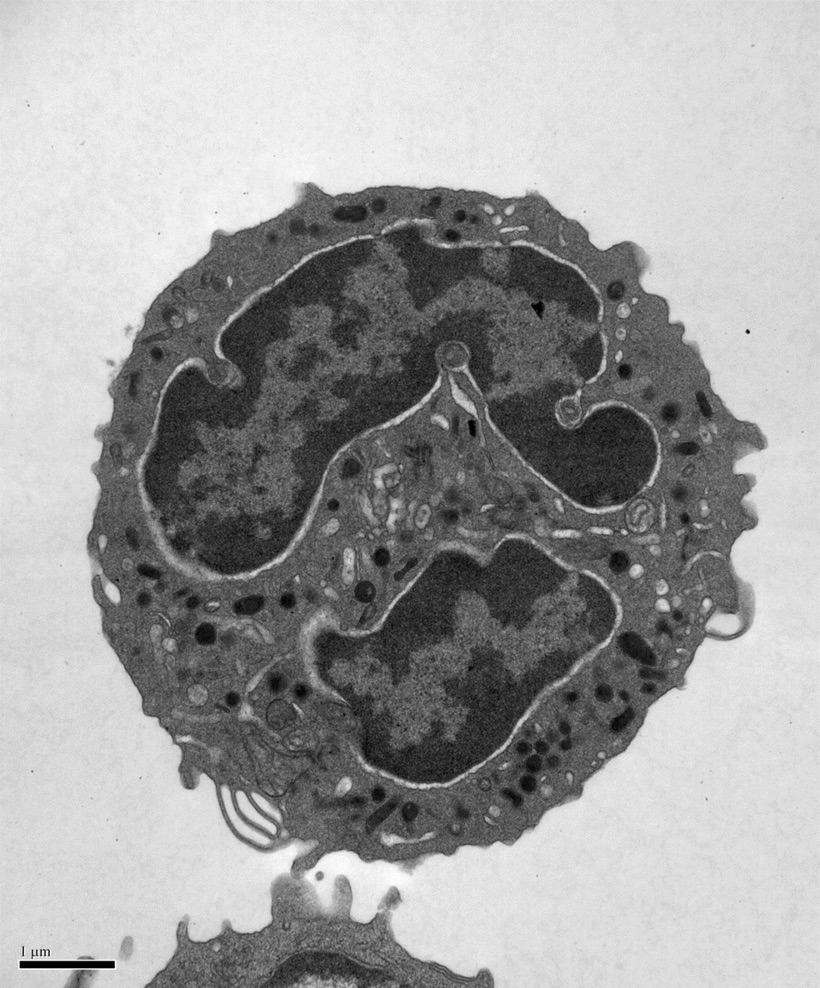

We are now applying our biochemical insights to understanding the human VPS45 and how dysfunctional point mutations in VPS45 lead to severe congenital neutropenia, bone marrow defects, and myelofibrosis in children. We are using a variety of techniques, in collaboration with Peter Newburger’s lab at UMass Chan to elucidate the mechanism behind this phenotype. These include biochemistry and structural biology methods to probe the effect of the mutations on the structure of VPS45 and its ability to interact with known binding partners; in complementary studies, cell biological techniques and fluorescence microscopy are used to understand the effect of the VPS45 mutations on cellular trafficking and organelle biogenesis. Mutant cells and mouse models are being developed using CRISPR/Cas9 technologies.